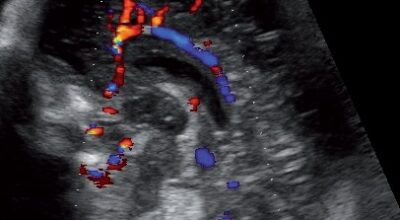

Ecografía de 17 semanas: placenta y origen del cordón umbilical. Gracias a la placenta se realizan los intercambios vasculares entre la madre y el feto. Bebé: coordina los movimientos de las extremidades. Los ojos se ubican hacia el frente de la cara. El feto mide 16 cm y pesa 155 gr.